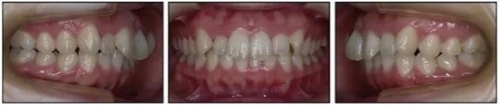

1.基本信息:女性,24歲2月,主訴上前牙及上唇不美觀(圖1)。因美觀問(wèn)題不愿使用上頜固定矯治器。

2.檢查:凸面型、骨性II類(lèi),安氏II類(lèi)1分類(lèi)錯(cuò)合畸形。面型正中對(duì)稱(chēng),下面高略高,頦部后縮,唇肌略緊張。無(wú)顳下頜關(guān)節(jié)癥狀,下頜運(yùn)動(dòng)正常,無(wú)偏斜。上下頜中線與面中線相一致,所有恒牙存在,口腔衛(wèi)生可,牙周情況可?;颊呓】?,無(wú)系統(tǒng)性疾病,無(wú)牙科創(chuàng)傷史及不良習(xí)慣,懷疑遺傳因素導(dǎo)致錯(cuò)合畸形。

3.測(cè)量分析:治療前記錄提示該患者左右磨牙與尖牙為安氏II類(lèi)關(guān)系,上頜牙弓重度擁擠,下頜牙弓輕度擁擠,深Spee曲線。6.3mm深覆蓋,80%深覆合。牙齒無(wú)齲,無(wú)第三磨牙。

頭側(cè)分析提示為骨性安氏II類(lèi)(ANB,8.4°;Wits,3.6mm),高角(SN-MP,44.9°),上頜切牙略舌傾(U1-SN,96.2°),下頜切牙略舌傾(IMPA,88。3°)(圖2;表)